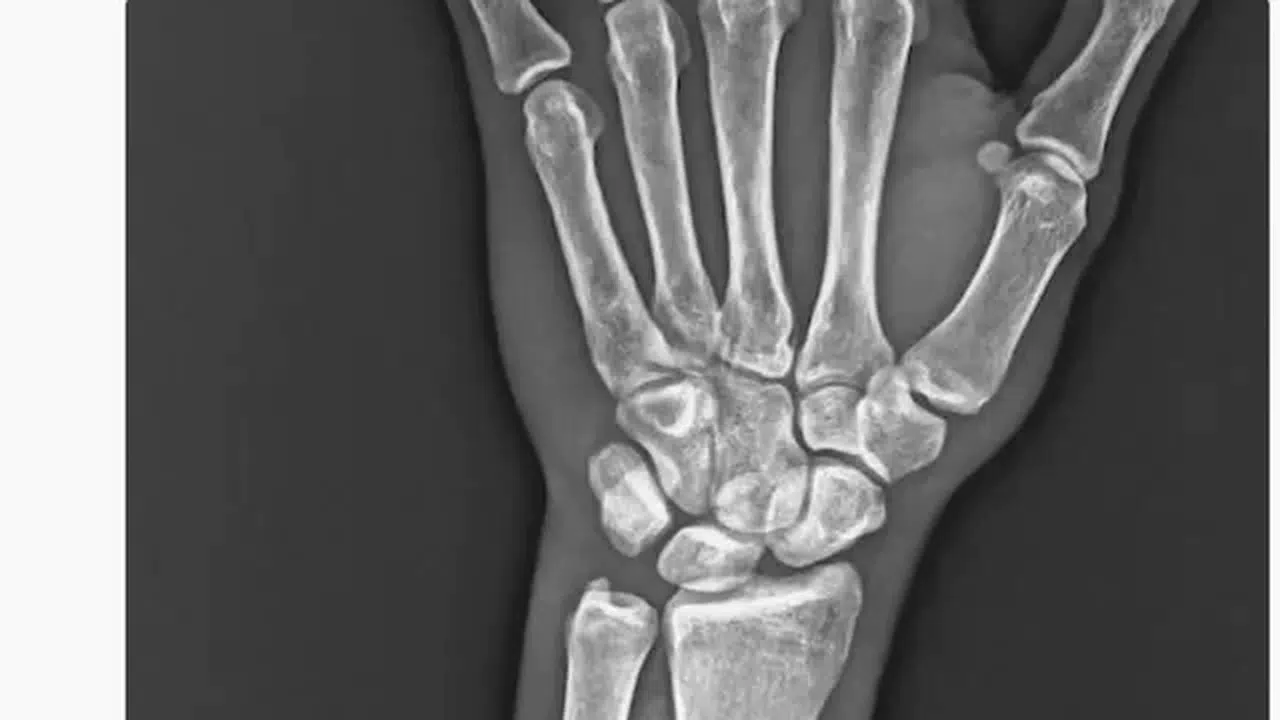

Trabzonspor'dan Onuachu'nun sakatlığına dair açıklama

Trabzonspor, Başakşehir ile oynadıkları maçta sakatlanan Paul Onuachu'nun sol kasık kas bölgesinde yaralanma ve sol ön kolda darbeye bağlı kemik kırığı tespit edildiğini açıkladı.

Trabzonspor, Başakşehir ile oynadıkları maçta sakatlanan Paul Onuachu'nun sol kasık kas bölgesinde yaralanma ve sol ön kolda darbeye bağlı kemik kırığı tespit edildiğini açıkladı.Trabzonspor Sağlık Kurulu Başkanı Doç. Dr. Ahmet Beşir, Trabzonspor’un Başakşehir’i 1-0 mağlup ettiği Ziraat Türkiye Kupası Çeyrek Final maçında sakatlanarak oyundan sedye ile çıkan Paul Onuachu'nun sağlık durumuyla ilgili açıklamada bulundu. Beşir açıklamasında, "Futbol A Takımımızın RAMS Başakşehir ile oynadığı karşılaşma esnasında sakatlanarak oyundan çıkan futbolcumuz Paul Onuachu’nun yapılan muayenesinde sol kasık bölgesinde kas (adduktor kas grubu) yaralanması ve sol önkolda darbeye bağlı ayrışmamış kemik (ulna) kırığı tespit edilmiştir. Oluşan kırık sebebiyle oyuncumuza en az 6 haftalık tedavi programı uygulanacaktır. Oyuncumuzun tedavisine sağlık ekibimizce başlanılmıştır" dedi.Öte yandan bordo mavili kulübün resmi sosyal medya hesaplarından Onuachu'nun sakatlık anına ilişkin “VAR’da göremediğiniz pozisyonun röntgen görüntüsü. #AdaletinizBatsın” şeklinde paylaşımda bulundu.